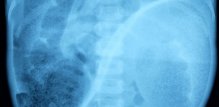

Hirschsprungova bolest – trajanje operacije